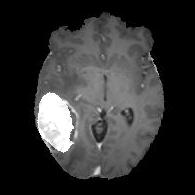

We argue that the sub-optimal paradigm of processing different abstractions within a single CNN pipeline can be remedied through the effective processing of information in a structured manner. Consequently, we devise strategies for disentangling the edge and texture information within a single training pipeline. Figure 2 illustrates how our proposed module, dubbed EG-CNN, can be paired with any existing CNN encoder-decoder to improve segmentation quality near intensity edges. We have applied our EG-CNN to the tasks of brain and liver tumor segmentation in medical images (Figure 3).

(1) Brain MR (2) Liver MR (3) Liver CT (4) Lung CT